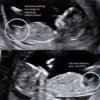

tajniki-pracy-ginekologa.jpg

• tajniki-pracy-ginekologa.jpg

40,6 KB · Wyświetleń: 390